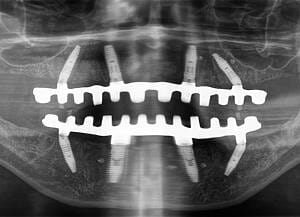

Natalie’s treatment began with a comprehensive clinical assessment, including a review of her medical and dental history, a full examination, and analysis of her functional difficulties such as her tongue habit and altered bite. A 3D cone-beam CT scan was then taken to assess bone quality and volume, identify areas of infection, and map important anatomical structures to ensure safe implant placement.

All data were transferred into digital treatment planning software, allowing virtual placement of implants and collaboration with the dental laboratory before surgery. This enabled careful evaluation of long-term outcomes and ensured the design of provisional and final prosthetics could be completed with precision. Following these discussions, the decision was made to proceed with the Fixed-Teeth-in-a-Day approach using the All-on-4 technique.